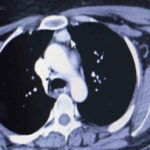

Amasya’da ayak tabanındaki yanma ve kaşıntıların giderek artması şikayetiyle hastaneye başvuran kadına, 100 binde 1 kişide görülen bir hastalığın teşhisi konuldu. Vücuda kalsiyum salgılayıp düzeyini kontrol eden 4 paratiroid bezinden biri, normalde olması gereken boyun yerine hastanın kalbinin üstünde bulundu. 3,4 kat büyümesiyle hastanın sağlığını tehdit eden kitle, başarılı bir ameliyatla alındı.

Amasya’nın Göynücek ilçesine bağlı Karaşar köyünde yaşayan evli ve 3 çocuk annesi Emine Şahin’in Amasya Üniversitesi Sabuncuoğlu Şerefeddin Eğitim ve Araştırma Hastanesi’nde yapılan kontrollerinde normalde boyun kısmında olan paratiroid bezlerinizden biri göğüs kafesi içinde kalbe yakın bir noktada tespit edildi. Amasya Üniversitesi Tıp Fakültesi Dekanı Prof. Dr. Cafer Polat, Dr. Öğretim Üyesi Suat Evirgen ve göğüs cerrahisi ekibinin katılımıyla gerçekleştirilen ameliyatla kitle vücuttan çıkarıldı. 50 yaşındaki hasta şikayetlerinden kurtularak sağlığına kavuştu.

Dr. Evirgen, “100 binde 1 kişide ender rastlanan ve bölgemizde ilk defa yapılan bir ameliyatı gerçekleştirdik. Çünkü Emine hanımın paratiroid adenomu normalde bulunması gereken boyun bölgesinde değil de göğüs boşluğu içindeydi. Bu bezler vücuda hormon salgıladığı için kemik erimesine, kanda kalsiyum artışına sebep oluyor. Bu tür hastalardaki şikayetlerin sebebi de zaten bu bezlerin büyümesidir” diye konuştu.